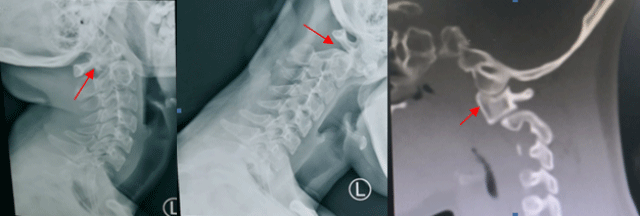

正常人體脊柱由24塊椎骨組成,其中頸椎7塊,胸椎12塊,腰椎…

擅長脊柱、關(guān)節(jié)及各類復(fù)雜、疑難骨科疾病的診療,開展各類骨科手術(shù)近萬例,技術(shù)精湛。尤其擅長治療各型頸椎…

擅長治療脊柱退變性疾病、脊柱骨折、脊柱腫瘤。開展單孔鏡及雙通道脊柱內(nèi)鏡微創(chuàng)手術(shù)及開放手術(shù)治療頸椎病、…